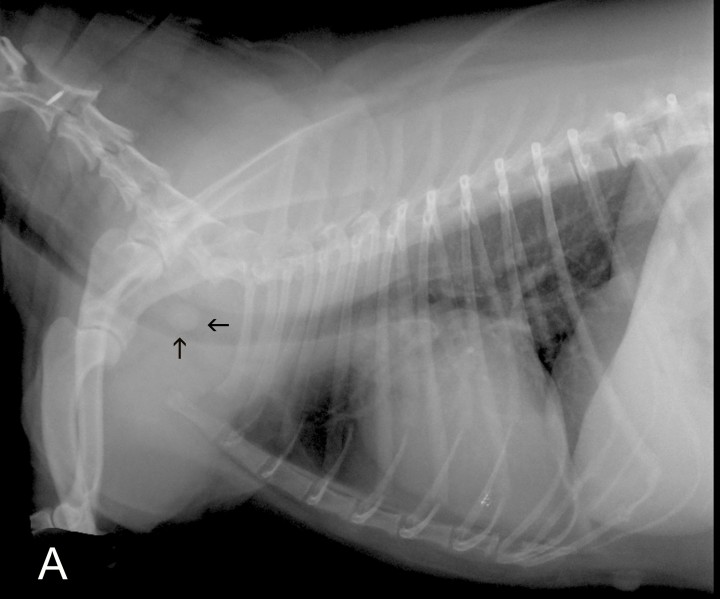

En la proyección lateral se visualiza una estructura de opacidad tejido blando y morfología redondeada en el interior de la luz traqueal en contacto con la pared dorsal de la tráquea, ocupando un 90 % de su diámetro, a nivel del cuerpo vertebral de C6. Tanto en la proyección lateral como en la ventrodorsal, el resto de la tráquea y la silueta cardiaca no presentan alteraciones evidentes y a nivel del parénquima pulmonar se aprecia un leve patrón bronquial (Fig. 2).

<p>Radiografía de la cavidad torácica en proyección lateral derecha de una perra mestiza de 7 años, en la que se visualiza un leve patrón bronquial y una estructura redondeada de opacidad tejido blando en el interior de la tráquea (flechas), a nivel del cuerpo vertebral de C6.</p>

Radiografía de la cavidad torácica en proyección lateral derecha de una perra mestiza de 7 años, en la que se visualiza un leve patrón bronquial y una estructura redondeada de opacidad tejido blando en el interior de la tráquea (flechas), a nivel del cuerpo vertebral de C6.